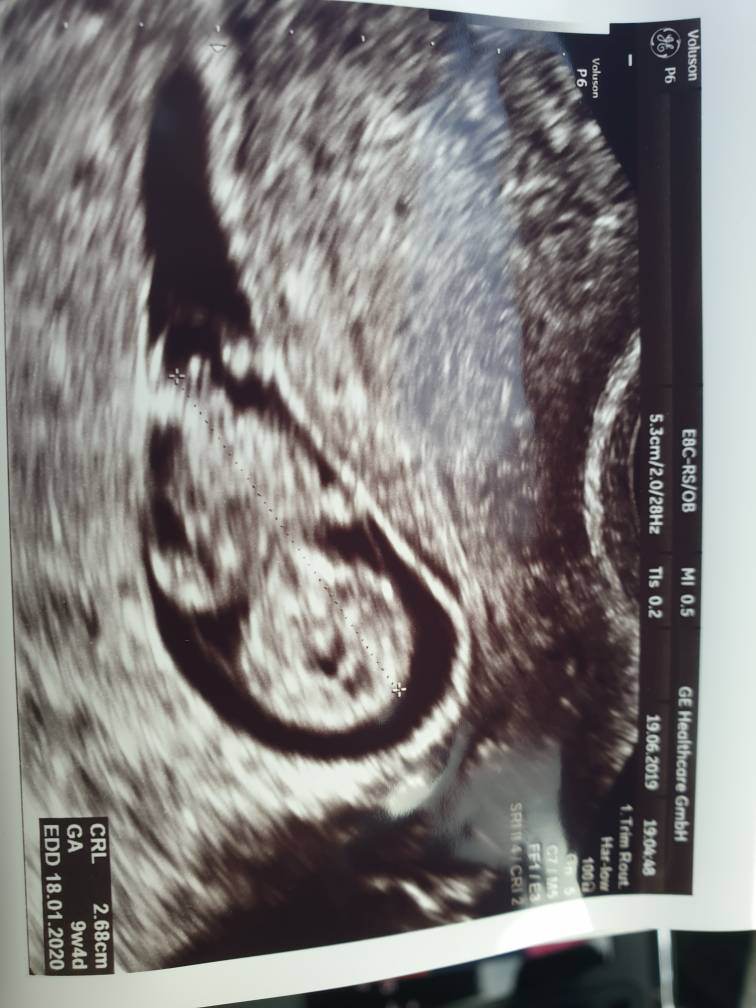

Ja też dzis odwiedziłam ginka

Dzidzi ma 2.68 i 9w4d

Krwiak jeszcze jest ale sie wchlania powoli. Dalej duphaston x2.

Dupek postraszyl mnie.. ze krwiak..ze wiek.. ze mam brac poprawke i takie tam

Prenatalne mam na 11.07

A NiftyPro umowione na 05.07.